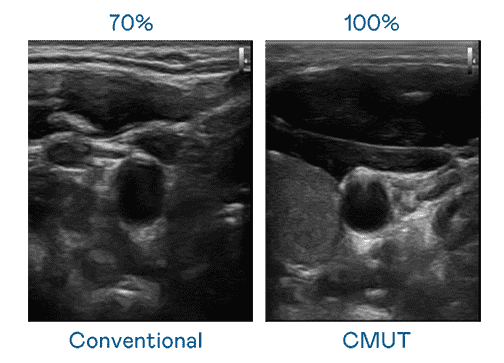

CMUT 技术是一种用电容式微机电元件来产生超音波讯号的技术。。与传统 PZT 压电式技术相比,,,CMUT 频宽增加 30%,,更宽频的超音波讯号让影像解析度大幅提升,,,,是实现高影像品质医疗超音波扫描、、、促进精准医疗发展的关键技术。。。

超音波影像的解析度高低,,,,首先取决于探头能发出的讯号频宽。。。MG电玩 CMUT 可提供高清晰的超音波讯号,,提供高频宽、、高灵敏度、、、影像纹理细节更高的超音波影像,,,,协助医护人员缩短影像判读时间及利用精准的医疗影像进行诊断。。。